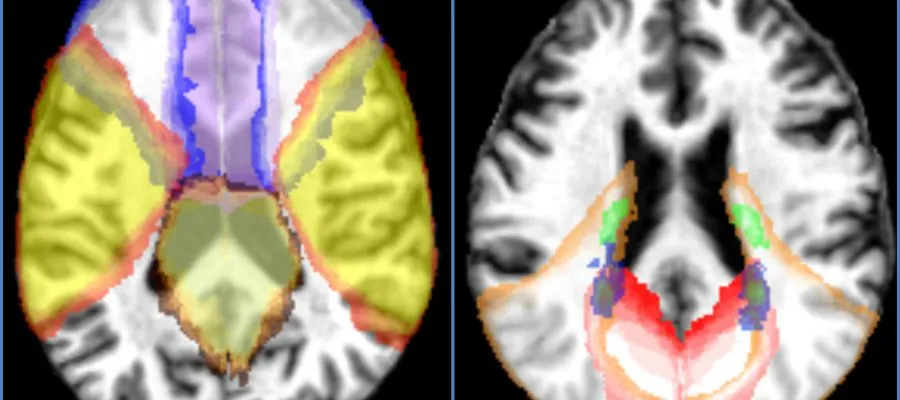

A preview of Edinburgh Science Festival 2017 Image The Easter holidays are approaching which means it’s almost time for the Edinburgh International Science Festival. As per previous years the College of Medicine and Veterinary Medicine is well represented in events for every interest and age group. Get connected The Edinburgh International Science Festival runs from April 1st to April 16th in venues right across the city. Organisers are encouraging attendees to get connected to science, each other and to the global community with the overall aim being for a sustainable future. There are plenty of engaging and hands on activities on offer for children and families but also talks, debates, screenings and workshops for adults too. Have a browse through the events below for opportunities to catch up with colleagues who are involved in this year’s festival. Image Moments in time exhibition If you pass by The Mound at any time during the Science Festival you may notice an array of iconic Scottish police boxes. Tying in with The 2017 Scottish Year of History, Heritage and Archaeology this exhibition celebrates Scotland’s fascinating past, greatest figures and iconic attractions. Where else would you expect to find Dolly the Sheep? If you delve into the correct police box you will find a showcase of current research from The Roslin Institute plus a tribute to our very own Scottish icon, Dolly. Find out more about the exhibition here Heart Attack: Sciences’s Battle of the Sexes Saturday 1st April Professor Nick Mills and Doctor Anoop Shah, both of the Centre for Cardiovascular Science will be leading a discussion on coronary heart disease, Scotland’s single biggest killer. They will be joined by a GP and a female heart attack survivor. Book tickets here Image A healthy philosophy: we need to talk about how we value our medicines Monday 3rd April Professor David Webb of the Centre for Cardiovascular Science will be on a panel of scientists discussing key questions such as: Who should we spend more money on medicines for, the elderly or the young? And should cancer be a special case? The audience will be asked which medicines they might like to fund and why. Book tickets here Connecting Codes to Cures and Amazing Immunology From Tuesday 11th April to Saturday 15th April you’ll find representatives from both Cancer Research UK Edinburgh Centre and the MRC Centre for Inflammation Research in the Learning Zone at the National Museum of Scotland. Children are invited to get hands on ‘to crack the secret code of DNA’ with the Cancer Research team and explore allergies, infections and vaccinations with researchers from the MRC CIR team. Find out more about Connecting Codes here and Amazing Immunology here Image Lothian Birth Cohort Project Tuesday 11th April Join researchers from the Centre for Cognitive Ageing and Cognitive Epidemiology to find out about the longest study of human cognition in the world, based right here at the University of Edinburgh. The study continues to analyse the intelligence of school children born in 1921 and 1936 and focusses on how childhood mental capacity affects health and cognitive function in later life. Book tickets here From séance to science: Who is psychology’s greatest hero? Friday 14th April Professor Thomas Bak of the Centre for Clinical Brain Sciences will join two of his colleagues from the School of Philosophy, Psychology and Language Sciences to discuss, debate and decide who played the biggest role in transforming pyscholgy from anecdotes into science. Each of the panel will argue who they consider to be the most important scientist in the history of psychology. Book your tickets here Image Dementia research and prevention: Illuminating brain changes Saturday 15th and Sunday 16th April Professor Craig Ritchie and Dr Tara Spires Jones will be discussing how the brain works, what goes wrong when people develop dementia and their work towards preventing and treating the condition. Following the talk attendees will be invited on a tour of the research laboratory within the Centre for Cognitive and Neural Systems at 1 George Square. They will be given the opportunity to operate microscopes and view the illuminated brain. After the tour there will be a reception and interactive forum where researchers will be on hand to answer and questions in a relaxed setting. Book tickets here Apr 01 2017 00.00 - Apr 16 2017 23.59 A preview of Edinburgh Science Festival 2017 The College has a strong representation at this year’s Science Festival. Here’s your quick guide to who, what, where and when. Various View the Edinburgh International Science Festival 2017 programme